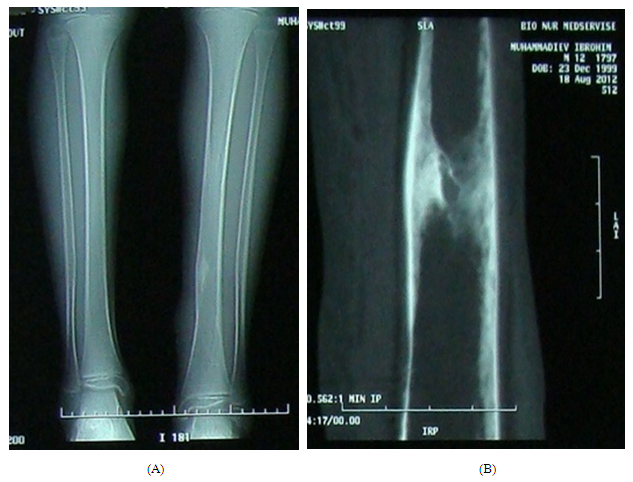

Statistic processing of the received results has been carried out with the use of the package of applied programs for biomedical investigations with calculation of the mean arithmetic (M), its errors (m) and standard deviation (σ). The reliability of the differences between two means (t) has been determined by Student-Fisher criterion with computer processing by Excel program.Computer tomography (CT) was included in the complex of preoperative diagnostics alongside with general clinic, laboratory and plan radiography in all patients. CT, in contrast of plan radiography, allowed determining more exactly the real sizes of destructive process in the injured bone (Figures 1 а, b). | Figure 1. General X-ray examination (А) And computer tomography (B) Of the right shin bone. It has been determined the presence of intraosseous abscess which clearly visualized on CT |